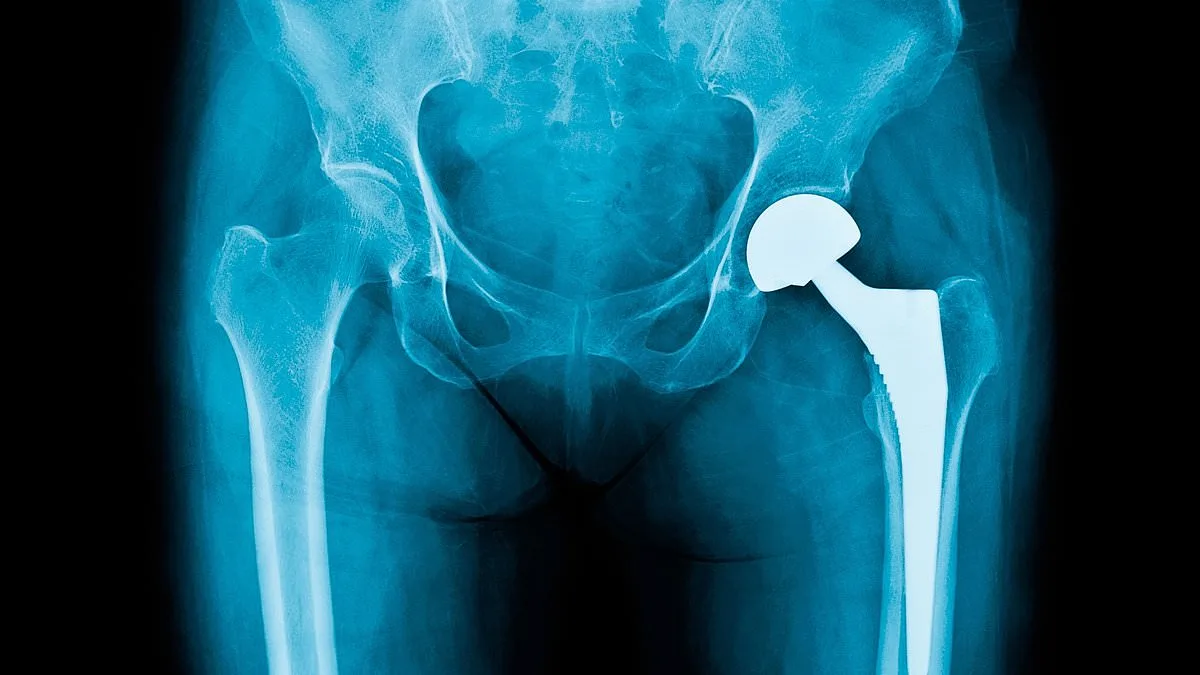

Bone cement plays a crucial role in joint replacement surgery, securing implants and enabling faster recovery. It is used in over 80% of knee replacements and nearly 60% of hip procedures, translating to 15,000 operations monthly. The disruption has raised alarms among patient advocacy groups, with Arthritis UK describing the situation as a 'crushing blow.' Dr. Alex Dickinson, a prosthetics engineering professor at the University of Southampton, explained that while alternatives exist, they require extensive development and clinical validation to ensure patient safety. 'Implant engineering is a cautious process,' he said. 'Any new technology carries risks, and thorough testing is essential to minimise harm.'